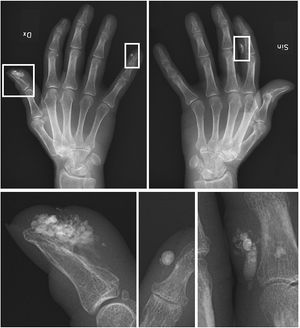

- Calcinosis(석회증): 피부가 두꺼워지고 팽팽해지며 칼슘 침착 결절이 생긴다.

피부가 두꺼워지고 팽팽해지며 칼슘 침착 결절(Calcinosis|칼시노시스영어)이 생긴다.[1]2. 2. 레이노 현상 (Raynaud's phenomenon)

가장 쉽게 인지할 수 있는 증상이지만, 모든 환자에게서 두드러지게 나타나는 것은 아니다. 일반적으로 피부가 두꺼워지는 현상은 CREST 증후군 환자의 손가락, 즉 손허리손가락 관절(metacarpophalangeal joint) 원위부의 피부에만 국한된다. 질병 초기에는 피부가 부어오르고 염증이 나타날 수 있다. 결국, 진피 섬유아세포가 과도하게 세포외 기질을 생성하여 피부에 콜라겐 침착이 증가한다. 콜라겐 가교 결합으로 인해 피부가 점차 조여든다. 손가락 원위부에 허혈성 궤양이 흔하게 발생하며, 환자의 30~50%에서 나타난다.[3]2. 5. 모세혈관 확장증 (Telangiectasias)